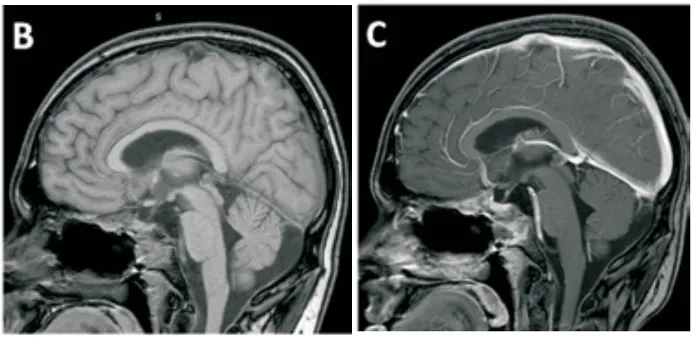

术后MRI检查证实肿瘤已获得完全切除。术后出现短暂的右侧外展神经麻痹,与术中发现相符。在启动全身性皮质类固醇治疗后,神经功能缺损迅速恢复。

术后影像评估:术后矢状位T1加权平扫及增强磁共振成像,证实肿瘤已获得完全切除。